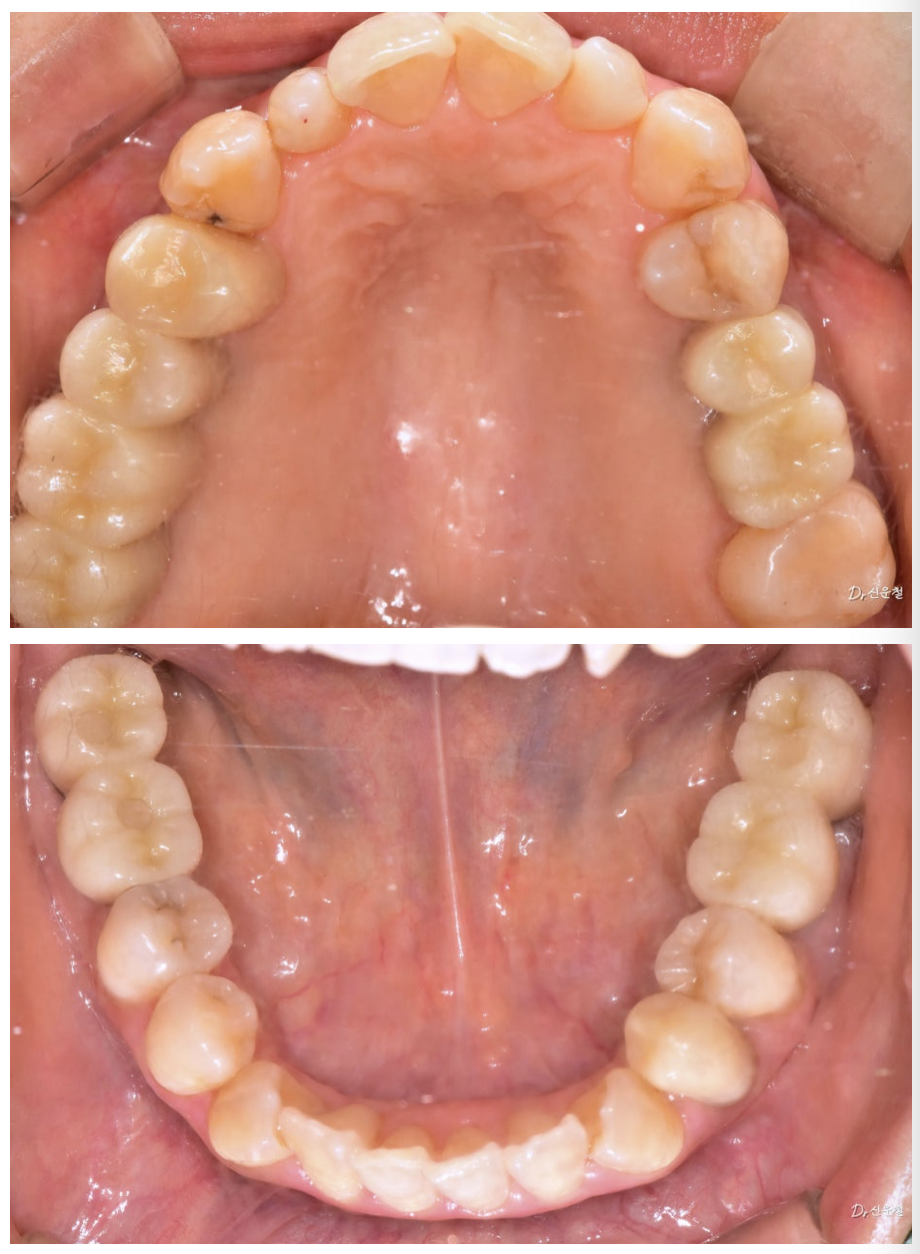

실제로 내원하신 30대 여성 환자분도

“아프진 않아요.”라고 말씀하셨습니다.

촬영일 250327

하지만 정밀 검진 결과, 깊게 진행된 사랑니 충치 뿌리만 남은 치아

잇몸뼈가 녹아 흔들리는 어금니 가 확인되었습니다.

통증이 없었던 것뿐,

문제는 이미 상당히 진행된 상태였습니다.

앞니만이 아니라 ‘웃는 전체’를 보셔야 합니다

웃을 때는 앞니만 보이지 않습니다.

어금니까지 함께 보입니다.

앞니 배열만이 아니라 어금니 충치, 보철 색감, 잇몸 라인까지

전체적인 밸런스를 함께 봐야 합니다.